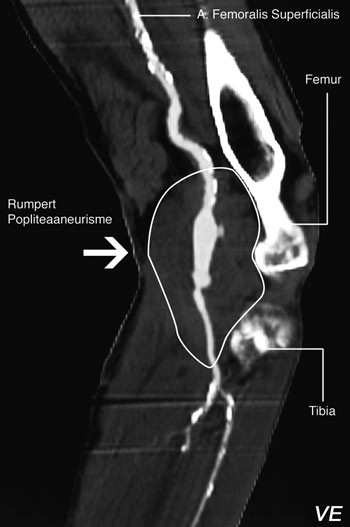

En 77 år gammel mann var gjennom en 12-årsperiode operert for aneurismer på bukaorta, bekkenarterier og arterier i lysker og knehaser. Han ble innlagt med dyp venetrombose i venstre lår og behandlet med warfarin. På grunn av økende hevelse og smerter i låret ble han overflyttet til Aker universitetssykehus 20 dager etter at symptomene debuterte. Etter ytterligere tre dagerble han operert med incisjon og evakuering av 800 ml illeluktende, brunfarget puss og nekrotisk vev. Vi fant også et rumpert aneurisme på venstre a. poplitea (fig 1). På høyre side var det likeledes et aneurisme, men det var ikke rumpert (fig 2). Infisert femoropopliteal bypass ble fjernet og erstattet med en ny bypass under kneleddet med snudd autolog vene.

På dag 17 ble det foretatt sirkulasjonsfysiologisk utredning. Dupleksundersøkelse viste et rumpert popliteaaneurisme med blødning ut av aneurismesekken på venstre side.

Pasienten ble operert 18. dag etter symptomdebut via medial tilgang. Det ble foretatt eksklusjon av aneurismet og femoropopliteal bypass nedenfor kneleddet med autolog snudd vene. Det ble videre gjort reseksjon av nekrotisk muskelvev i den mediale delen av musculus gastrocnemius, lukking av fistel mellom v. poplitea og aneurismesekken og fasciotomi i alle fire muskellosjer i venstre legg. Peroperativ blodstrømsmåling viste at det gikk 140 ml/min i a. femoralis superficialis. Dyrking fra sårsekret gav oppvekst av gule stafylokokker og koliforme staver.